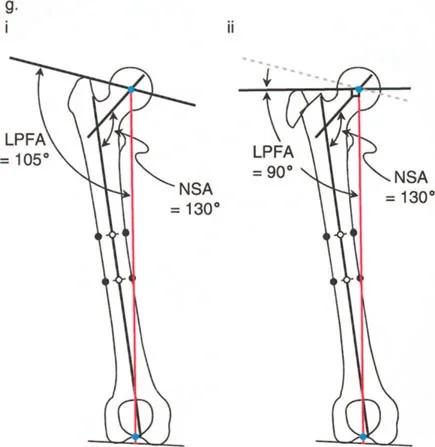

يستخدم جراحو العظام عدة زوايا لقياس محاذاة مفصل الورك وعظم الفخذ، وهي حاسمة في تشخيص التشوهات وتخطيط العلاج:

- الزاوية بين عنق وجسم الفخذ (Neck-Shaft Angle - NSA): هي الزاوية بين محور عنق الفخذ ومحور جسم الفخذ.

- الزاوية الطبيعية: تتراوح عادة بين 125° و 135°.

- كسع الورك (Coxa Vara): تحدث عندما تكون هذه الزاوية أقل من الطبيعي (أقل من 120°)، مما يجعل عنق الفخذ أكثر أفقية.

- فحج الورك (Coxa Valga): تحدث عندما تكون هذه الزاوية أكبر من الطبيعي (أكثر من 140°)، مما يجعل عنق الفخذ أكثر عمودية.

- الزاوية الميكانيكية لعظم الفخذ القريب (Mechanical Proximal Femoral Angle - MPFA): تقيس العلاقة بين محور عظم الفخذ ومستوى المدور الكبير.

- الزاوية الجانبية لعظم الفخذ القريب (Lateral Proximal Femoral Angle - LPFA): تقيس ميل الجزء العلوي من عظم الفخذ.

تؤثر هذه الزوايا بشكل مباشر على ميكانيكا مفصل الورك، وخاصة على ذراع الرافعة للعضلات المبعدة للورك. عندما تكون هذه الزوايا غير طبيعية، يزداد الضغط على المفصل، وتضعف العضلات، مما يؤدي إلى الألم والعرج وتآكل المفصل.

- قياس الزوايا: تحديد الزاوية بين عنق وجسم الفخذ (NSA)، والزاوية الميكانيكية لعظم الفخذ القريب (MPFA)، والزاوية الجانبية لعظم الفخذ القريب (LPFA). هذه القياسات حاسمة لتخطيط الجراحة.

- الهدف: زيادة الزاوية بين عنق وجسم الفخذ إلى المعدل الطبيعي (125-135 درجة)، مما يطيل الطرف ويخفض المدور الكبير، ويحسن ذراع الرافعة للعضلات المبعدة للورك.

- الهدف: تقليل الزاوية بين عنق وجسم الفخذ، مما يزيد من ذراع الرافعة للعضلات المبعدة ويقلل الضغط على المفصل. قد يؤدي هذا إلى إزاحة المدور الكبير للأعلى، مما يستدعي إجراء نقل للمدور الكبير لتعويض هذا التأثير.